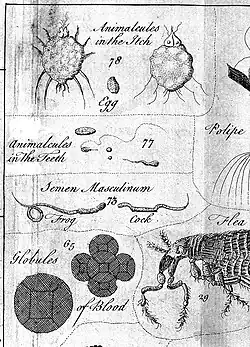

Histologie

Im 16. Jahrhundert interpretierte Volcher Coiter im Gegensatz zu Vesal und zu seinen Bekannten Eustachi und Falloppio den Zahn nicht mehr als Knochen.[119] In der vormikroskopischen Ära des 16. und 17. Jahrhunderts haben neben Bartholomaeus Eustachius auch Marcello Malpighi (1628–1694) und Johann Jakob Rau (1668–1719) die Zahnhartgewebsstrukturen und ihre Entstehung erforscht. Mit der Entwicklung optischer Vergrößerungshilfen, vor allem durch Antoni van Leeuwenhoek (1632–1723), werden genauere histologische Untersuchungen der Zahnhartsubstanzen und Entdeckungen im Bereich der histologischen Abläufe während der Embryonalphase der Zähne möglich. Malpighi postuliert die Sekretionstheorie der Schmelzentstehung mittels eines verknöchernden Saftes, bei Eustachius findet sich erstmals die Erwähnung der Umwandlungstheorie. Alexander Nasmyth (1789–1849), Richard Owen (1804–1892), Anders Adolf Retzius (1796–1860), Jan Evangelista Purkyně (1787–1869), Albert von Koelliker (1816–1905), Wilhelm von Waldeyer-Hartz (1836–1921), Viktor von Ebner-Rofenstein (1842–1925), Gustav Preiswerk (1866–1908), John Tomes (1815–1895) ebenso wie sein Sohn Charles (1846–1928)[120] und viele andere Forscher gaben damals der Zahnhistologie durch gründliche Bearbeitung des gesamten Gebietes die breite wissenschaftliche Basis.[121]

Wenn in der Neuzeit der makroskopische „Zahnwurm“ belächelt wird, so erscheinen in den Mikroskopen der Neuzeit die Bakterien und Pilze zweifellos wurmähnlich.